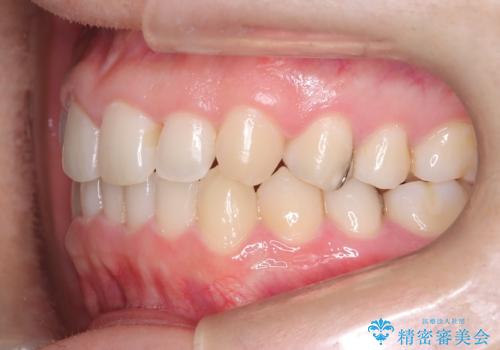

- 下の歯のがたつき(叢生)、真ん中(正中)が右にずれていることを主訴に来院されました。右上前から3番目の永久歯が埋まっている(埋伏)していることから正中は可能な限り合わせることをゴールとしてマウスピースでの矯正治療を選択しました。

今回の矯正治療では、透明なマウスピース型の装置インビザラインを使用しました。がたつきをとるため、安全性が確保できる範囲で歯と歯の間を少し削り必要なスペースを確保しました。